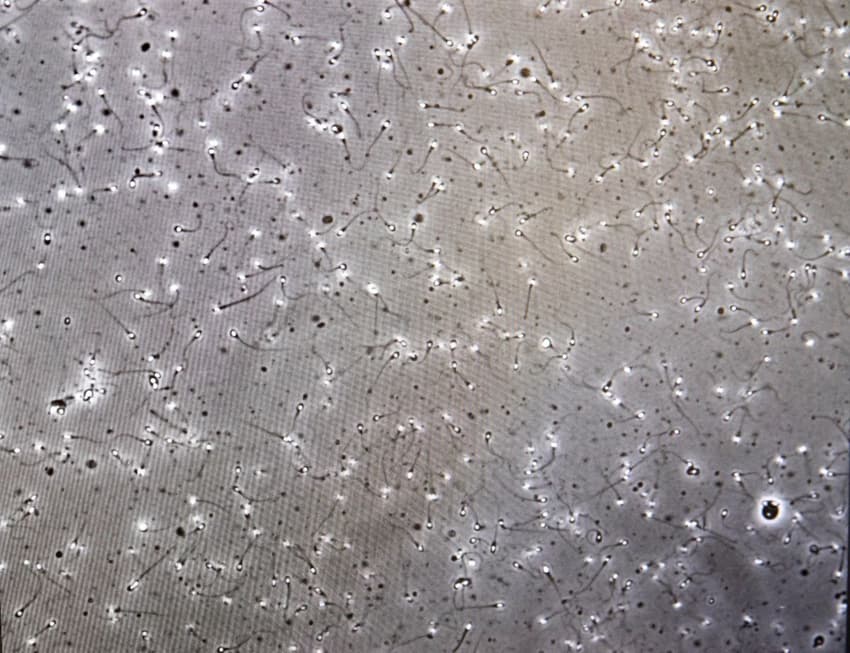

At least five men in Sweden have unwillingly fathered children after their sperm was used for fertility treatments without their permission.

In March, Uppdrag Granskning, the investigations programme run by public broadcaster SVT, reported on the so-called "sperm theft" at the hospital, which took place between 1985 and 1996.

A doctor at the hospital appears to have used sperm collected for sperm tests as donor sperm in fertility treatment without informing the donors, leading to at least five men becoming fathers unknowingly.

It has only been since DNA testing became more widespread that it has been possible to connect the children with their real fathers.